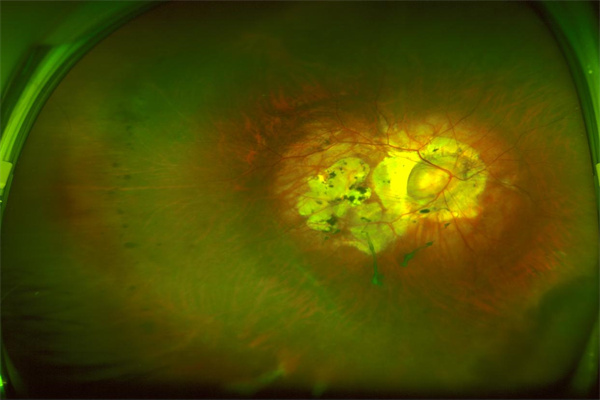

糖尿病視網(wǎng)膜病變

近視患者(特別是大于600度的高度近視):近視患者因眼球結(jié)構(gòu)變化應密切關(guān)注眼底健康,近視患者應做到至少每年檢查一次眼底,度數(shù)越高眼底病變風險越大,檢查頻次也應相應提高。此外,中老年近視患者也應提高其檢查頻次。

高度近視眼底